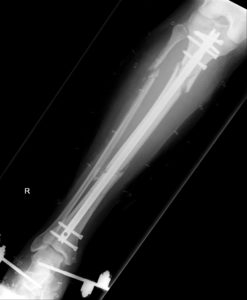

Tibial nail surgery is performed on patients who have broken their tibia bone – one of the two lower leg bones – and require surgical intervention in the means of a metal rod being inserted to fix the bone and aid the healing process.

Jason has now been discharged to recover further at home in Essex. The x-ray below shows the nail in place post-surgery.